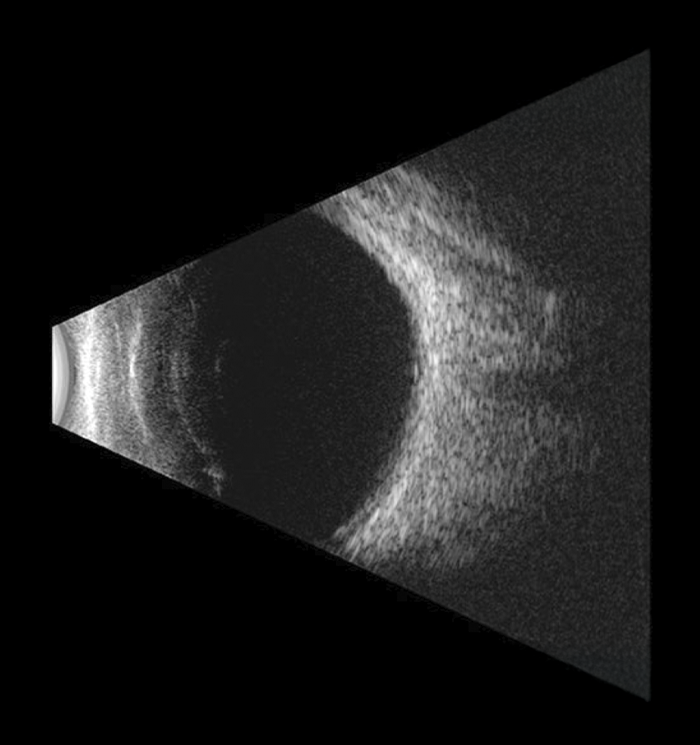

Visualización detallada de las estructuras internas del ojo

Ultrasonido ocular

El ultrasonido ocular utiliza ondas sonoras de alta frecuencia para obtener imágenes de las estructuras internas del ojo que no se observan en una exploración clínica convencional.